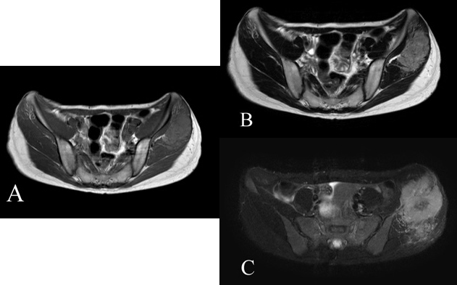

The case reported here is about a 30-year-old woman, who presented with a 6-month history of left buttock pain. She had no major past history. On physical examination, swelling and skin redness were observed on her left buttock. Further, an antero-posterior radiograph of the pelvis revealed the presence of osteolytic lesion in the left iliac crest (Figure 1A) and computed tomography (CT) revealed a destructive and moth-eaten appearance in the ilium as well as the presence of soft tissue mass on both sides of the bone (Figure 1B). Furthermore, magnetic resonance angiography (MRA) revealed diffuse hyper-vascularity in the lesion (Figure 2A), and axial non-enhanced T1-weighted magnetic resonance imaging (MRI) of the lesion revealed a homogeneous higher signal intensity than the adjacent muscle. On both T2-weighted image and short tau inversion recovery (STIR) images, the high signal intensity predominantly denoted the lesion, while the low signal intensity corresponded to the central portion and flow voids (Figure 3). Additionally, based on MRI, the tumor measured 48×63×73 mm. These radiological findings strongly suggested the presence of a malignant bone tumor, possibly Ewing sarcoma or lymphoma.

Figure 3: Axial T1-weighted MRI image revealing a higher signal intensity for the lesion than for the surrounding muscle in both intramedullary and extraskeletal tumors (A). T2-weighted and STIR images indicating that most of the tumor showed high signal intensities and occasional spotty low intensities (flow voids) (B, C). Central portion in the lateral soft tissue mass showing low intensity on all three sequences indicative of tumor necrosis (A–C).

Osteolytic lesions, such as destructive or moth-eaten appearance in plain X-ray or CT images and soft-tissue masses in CT or MRI images, are the common radiological features in all ASPS cases [4],[5],[7],[8],[9],[10] (Table 1). These findings are common to primary malignant bone tumor, such as osteosarcoma, Ewing sarcoma, and lymphoma. However, the distinctive MRI features of ASPS are intermediate-high signal intensity in T1-weighted images and high signal intensity in T2-weighted images. In three of the six previously reported cases, signal voids and/or low signal intensity in the central necrosis were observed [5],[7]. These MRI findings are similar to that of soft tissue ASPS [11],[12].